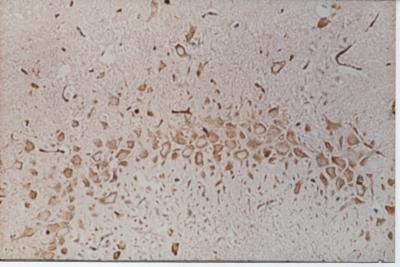

In the pretreatment group, there were more vascular endothelial growth factor-positive cells in the hippocampal CA3 region of cerebral infarction rats (immunohistochemical staining)

(Photo Credit: Neural Regeneration Research)